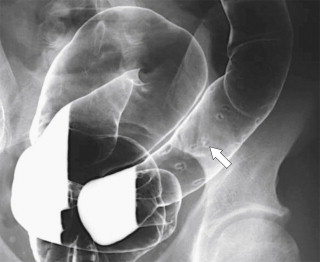

Plain radiography may demonstrate an ileus, sometimes confined to the left colon. As the disease progresses, bowel wall thickening develops ( Fig. 5-34 ) with a toxic megacolon if severe ( Fig. 5-35 ). BE is now rarely performed, but results demonstrate thickened folds and ulceration, either linear or with mucosal sloughing. Healing can lead to stricture formation ( Fig. 5-36 ). The findings are now usually made by CT and are similar to other forms of colitis (inflammatory bowel disease, infectious colitides, and radiation colitis if the radiation field included the colon). The disease is suggested in the appropriate clinical setting and by the left-sided distribution of the colonic changes ( Fig. 5-37 ). Severely affected patients show colonic pneumatosis as the gas permeates the damaged mucosa, which can then enter the mesenteric venous system and be recognized as mesenteric venous gas (particularly at CT) and ultimately intrahepatic portal venous gas. Occasionally, ischemia occurs proximal to an obstructing colonic stricture, such as colonic adenocarcinoma. The obstruction causes marked distention of the proximal colon, compromising its vascular supply or directly invading mesenteric vasculature ( Fig. 5-38 ).

Figure 5-36, BE in a 71-year-old man with a left mid-descending colon stricture ( arrow ) secondary to fibrosis from prior ischemic colitis.